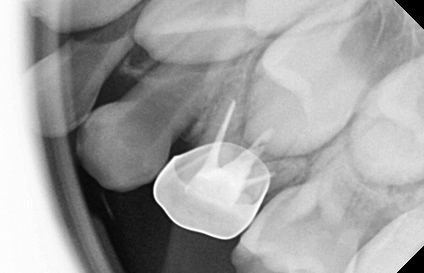

• 기성 금속관 수복

스테인리스로 만들어진 은색의 기성 크라운 보철로,

충치가 심하거나 신경치료한 유치 어금니를 전체적으로 씌워 보호하는 치료입니다.

유치 신경치료는 일반적으로 2회 내원 신경치료 및 크라운 치료까지 마무리 됩니다.

• 1차 내원

1차 내원에서는 국소마취 후 충치와 감염된 신경을 제거한 다음,

충전재를 넣고 코어(core)를 형성합니다.

• 2차 내원

2차 내원에서는 국소마취 후 치아 모양을 정리하고,

미리 만들어진 크라운을 치아에 맞게 조정한 후 접착하여 마무리합니다.